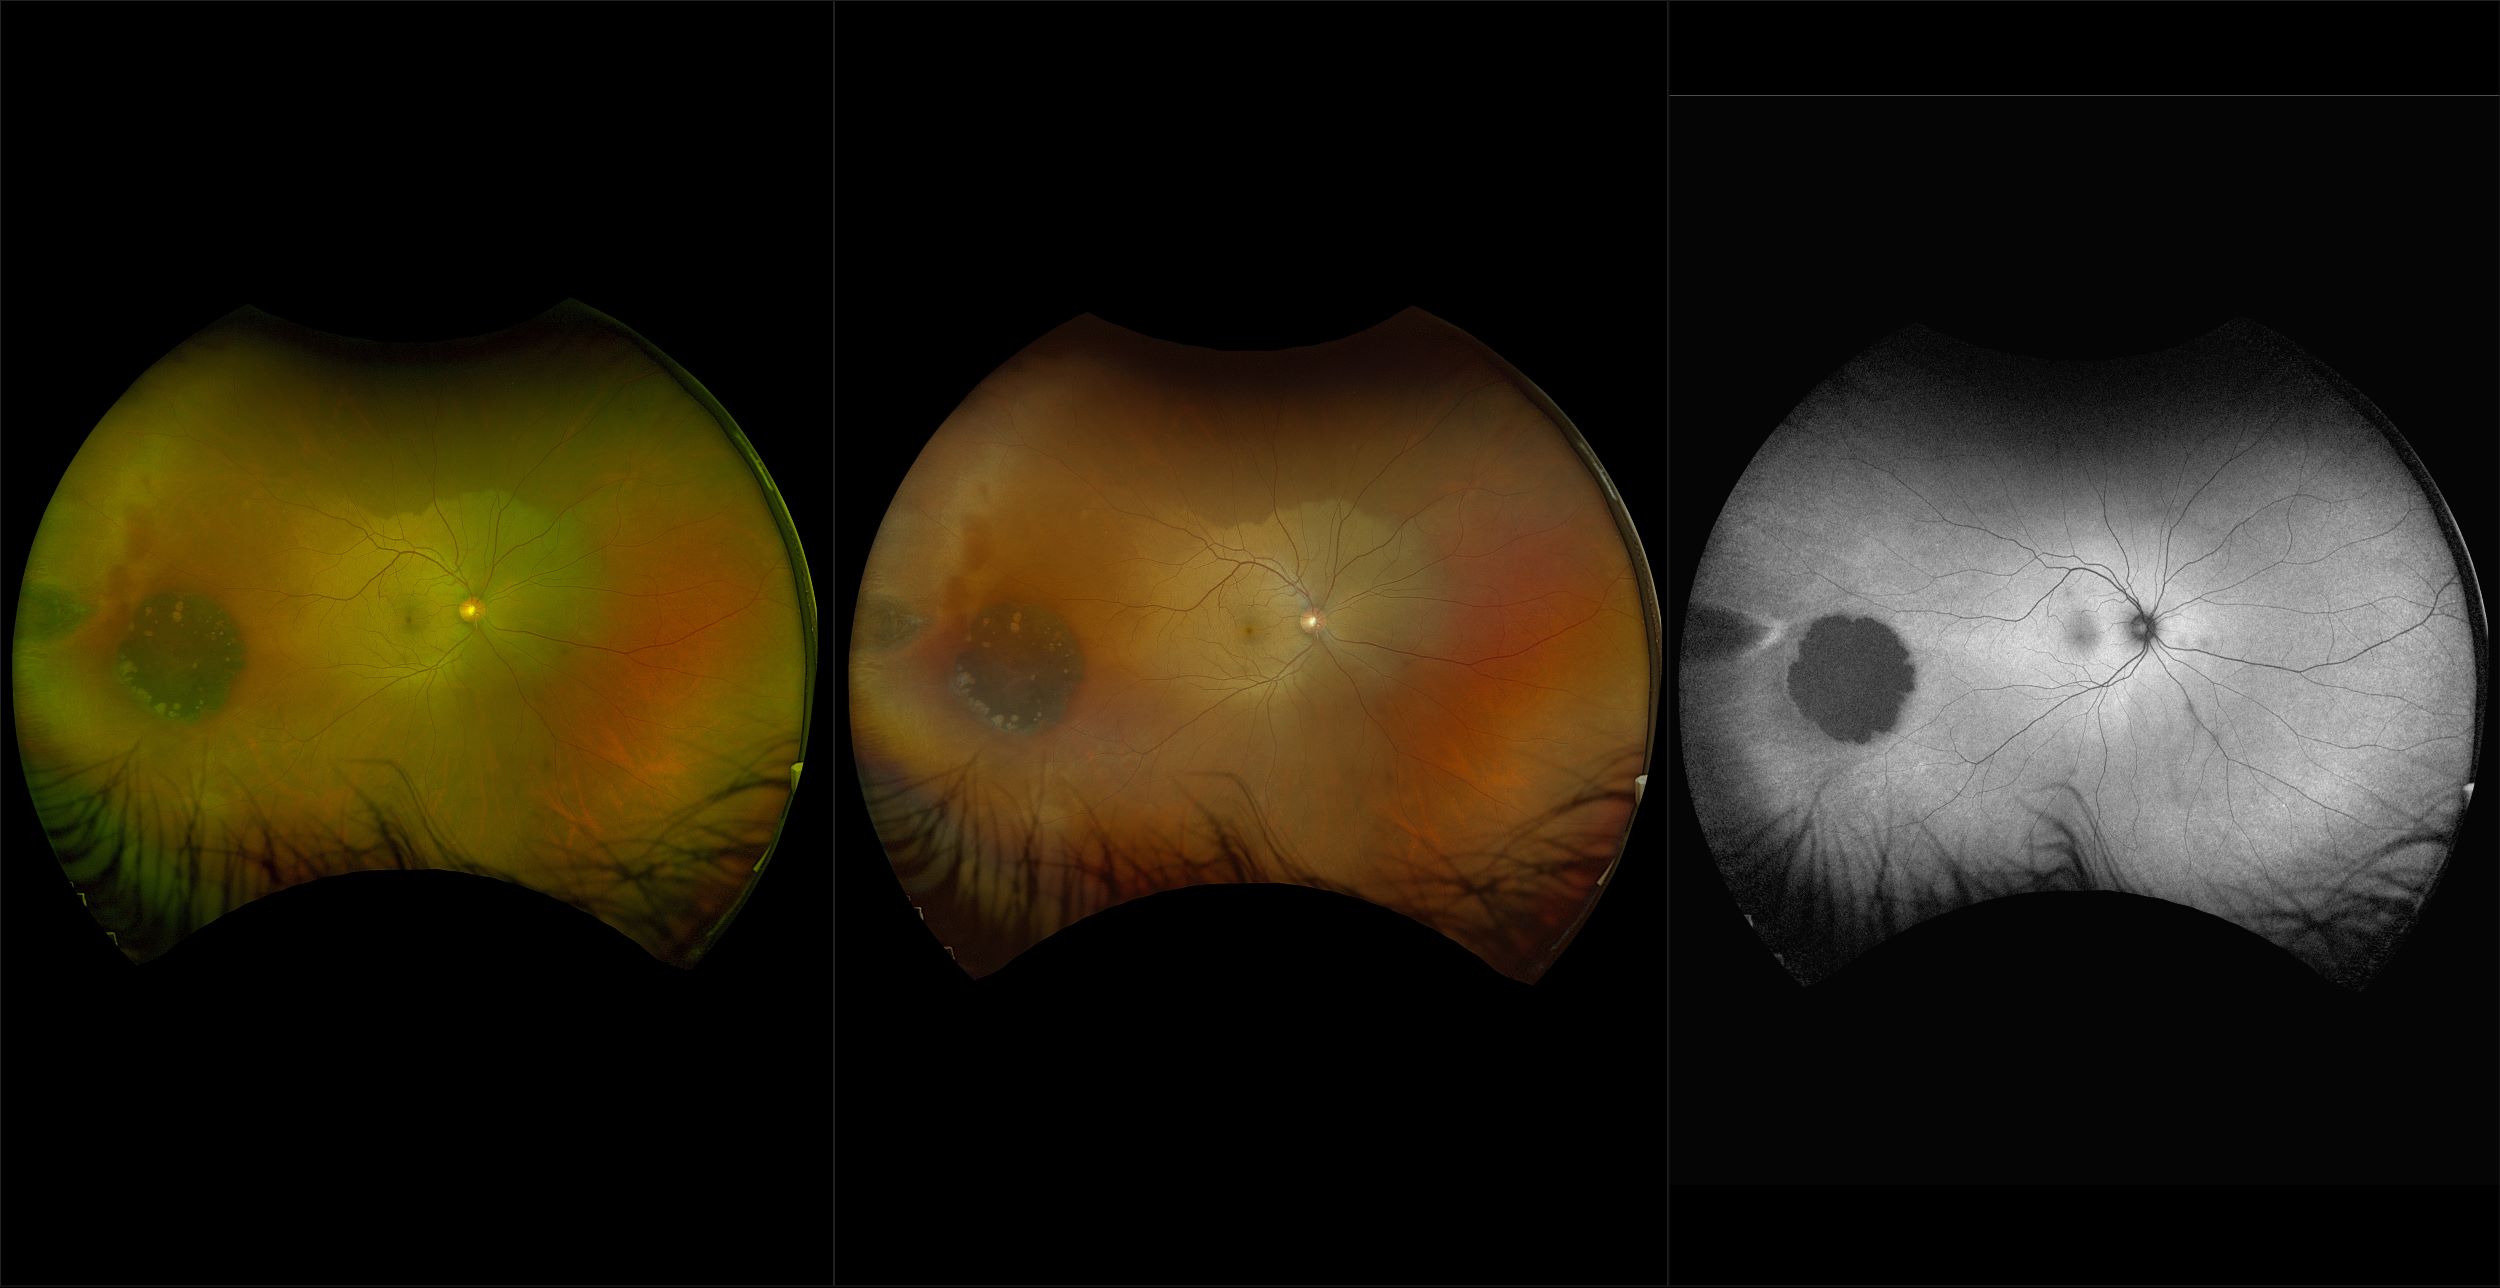

California - Choroidal Nevus, RG, AF

A choroidal nevus is simply an accumulation of melanocytes in the choroid. They are a space occupying mass or a benign melanoma. Choroidal nevi are slate gray in color, have indistinct margins, and may be slightly elevated (1-2 diopters). Since they are in the choroid, they are usually only seen in the red separation and not the green. The green separation may show the RPE degeneration associated with nevi which is seen as pigment mottling and drusen.